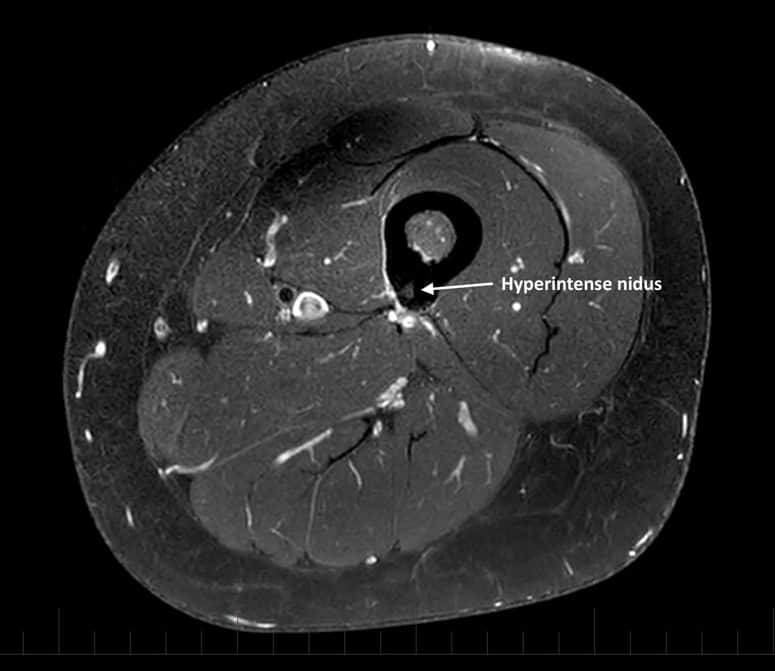

U dạng xương

» Thông tin: Nữ giới – 23 tuổi.

» Lâm sàng: Đau xương đùi 6 tháng.